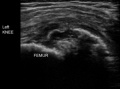

(B) Ultrasound of same patient showing cortical destruction and boney mass.